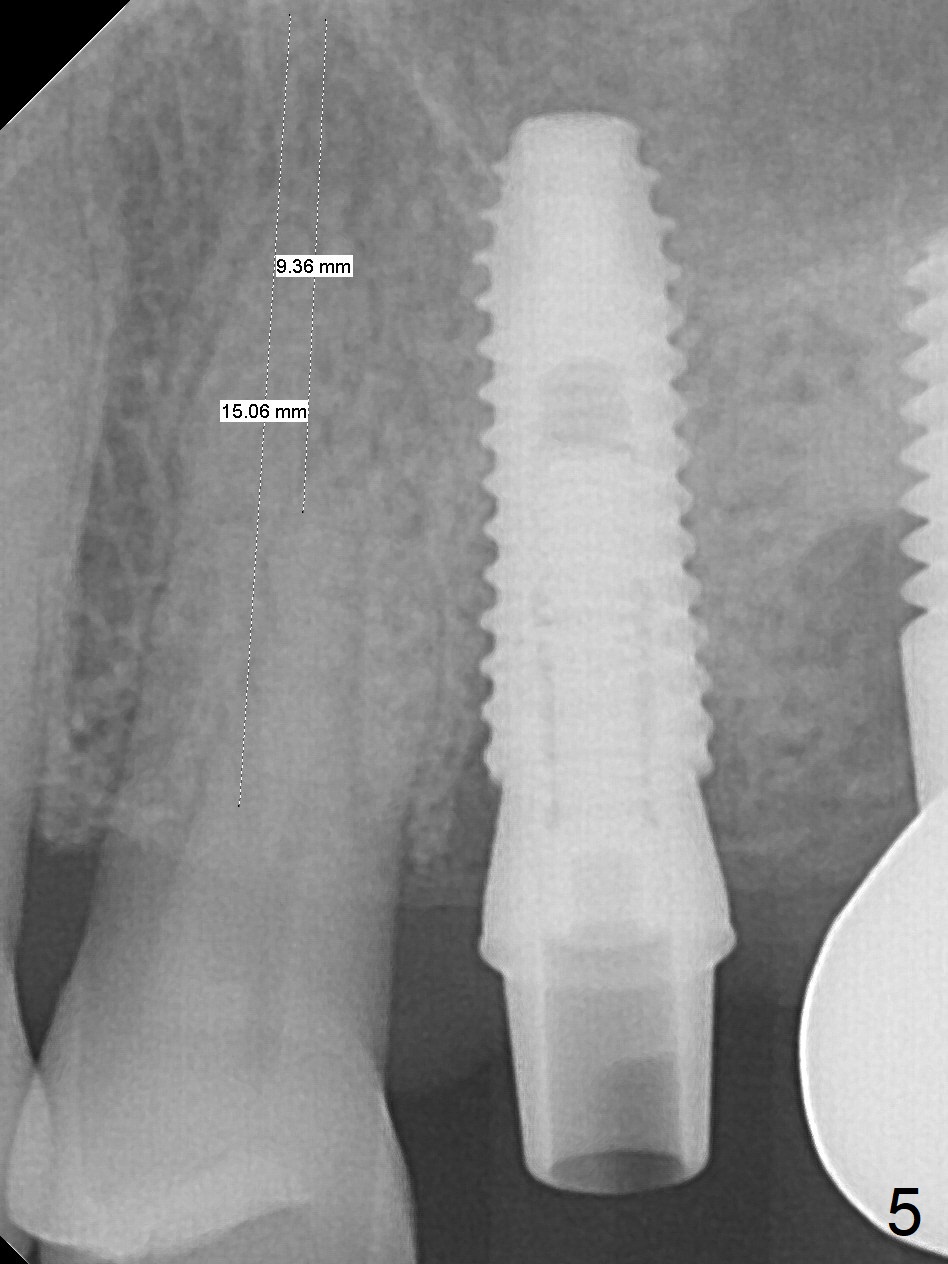

The tooth #12 is found to have crack 3 months postop. Initial depth will be 17 mm for 3.8x13 mm implant (Fig.5; Clindamycin). The tooth has two roots (Fig.3). Osteotomy is to be created in the septum.